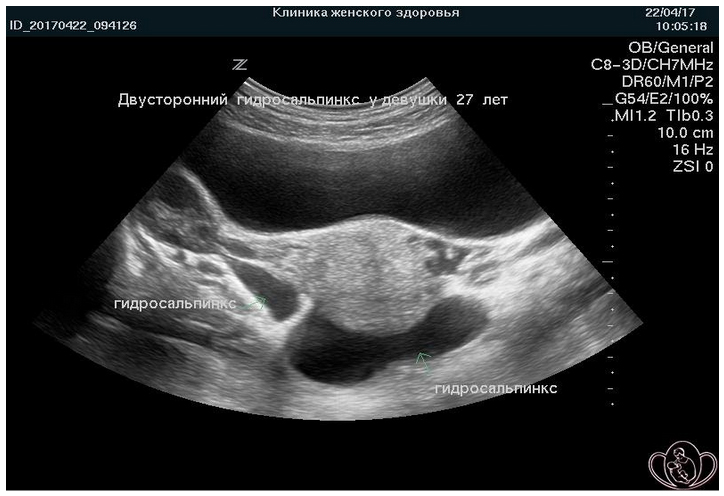

По локализации различают: односторонний (правый или левый) и двусторонний сактосальпинкс, в зависимости от того, вовлечена ли в патологический процесс одна или обе фаллопиевы трубы.

- УЗИ органов малого таза.